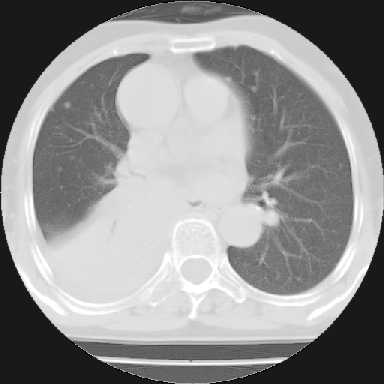

以下是引用苯小孩在2007-4-13 16:20:00的发言:[br]1、右下肺中央型肺癌并阻塞性肺不张、肺内转移、胸椎右侧附件亦有转移<横断层面第8层>.[br]2、右侧胸腔积液.

以下是引用swyyy2007在2007-4-13 15:31:00的发言:[br]右肺门下区肿块,右肺下叶支气管阻塞,右肺下叶不张,右侧大量胸腔积液,右肺中叶见结节状高密度影,边缘清,纵隔内见肿大淋巴结。首先考虑右下肺中心型肺癌伴右肺下叶不张、中叶、纵隔淋巴结转移。右侧胸腔积液。